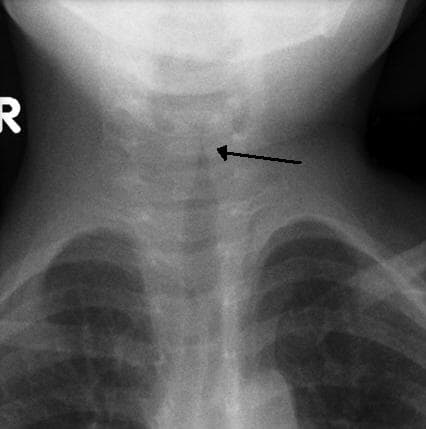

Le croup (ou laryngo-trachéo-bronchite) est une affection respiratoire habituellement déclenchée par une infection virale aiguë des voies aériennes supérieures. L'infection conduit à un gonflement de l'intérieur de la gorge, qui gêne la respiration normale et produit les symptômes classiques : toux dite « aboyante », stridor, dysphonie. Le croup peut produire des symptômes légers à sévères, souvent aggravés la nuit. Il est souvent traité par une dose unique de stéroïdes oraux. Occasionnellement, l'adrénaline est utilisée si le cas est sévère. L'hospitalisation est rarement requise. Le croup est diagnostiqué cliniquement, une fois exclues les autres causes potentielles et plus sévères des symptômes, telles que l'épiglottite ou la présence d'un corps étranger dans les voies aériennes. Des recherches plus poussées, comme les tests sanguins, radiographies ou cultures sont rarement indispensables. Il s'agit d'une affection relativement commune qui peut affecter jusqu'à 15 % des enfants à certains endroits, le plus souvent entre 6 mois et 5-6 ans. Il n'est presque jamais observé chez les adolescents ou les adultes. Bien qu'originellement attribué à la diphtérie, cette étiologie est aujourd'hui peu fréquente dans le monde occidental grâce au succès de la vaccination. Le croup se caractérise par les symptômes suivants : toux « aboyante », stridor, dysphonie et une gêne respiratoire aggravée la nuit. La toux « aboyante » est souvent décrite comme ressemblant au cri du pinnipède ou du lion de mer. Le stridor est aggravé par l'agitation ou les pleurs et, s'il est présent au repos, il indique un rétrécissement critique des voies aériennes. Tandis que le croup s'aggrave, le stridor peut décroître considérablement. Les autres symptômes incluent fièvre, coryza (symptômes typiques du rhume) et tirage costal ou inter-costal. L'hypersialorrhée ou un état général très dégradé indiquent d'autres affections. Le plus souvent, le croup est dû à une infection virale.